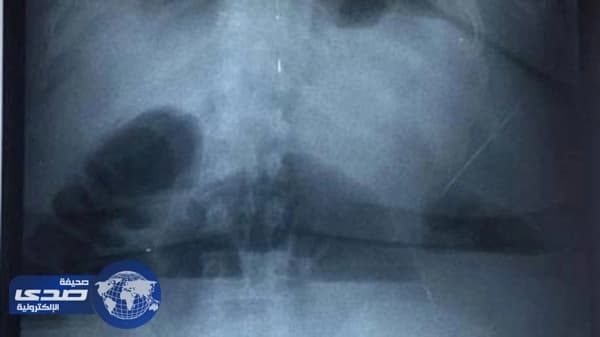

من جانبه، قال مسؤول إعلام المستشفى، كرمانج محمد إن “المريضة أكدت أنها كانت تتناول بين 20 إلى 25 منديلاً ورقياً يومياً لخفض الوزن منذ الـ 10 مارس2017، وأنها أصيبت بألم حاد في بطنها منذ مساء الثلاثاء، ومن المحتمل أن يتطلب علاجها إجراء عملية جراحية لها”.